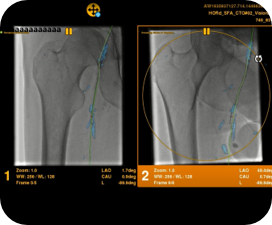

Planifier

Guider

Évaluer